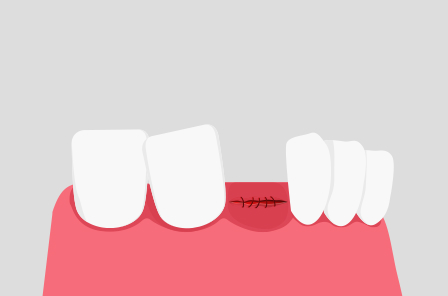

STEP 3

잇몸 봉합

발치 후 절개 부위를 봉합합니다.

3~4일간 통증이 지속될 수 있으므로 처방전에 따라 진통제를 복용합니다.